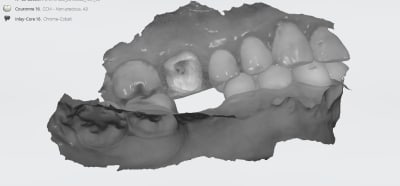

IC ceram 23 + stellite.

Idem que Chicot: Oneshot mais avec un peu plus d’éléments : 3IC, 8 CCM, 1 Stelitte. Aucune retouche autre qu’occlusale. Même Labo, c’est basique mais efficace